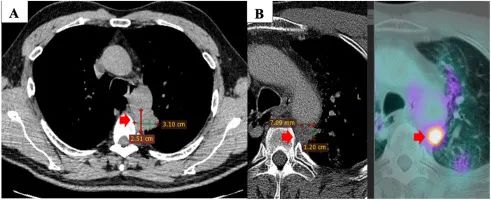

2019 年 5 月,一名 60 歲男性患者,無吸煙史,有咳嗽、背痛和疲勞癥狀,被診斷為非小細胞肺癌癌癥。CT 顯示原發性腫瘤位于左上葉 31×1 mm,侵犯主動脈周圍縱隔組織??v隔內出現數個淋巴結,最大尺寸為 15×5 mm,右肺上葉有 7 個淋巴結顯示,大小分別為 4 mm 和 2 mm。CT 引導下的結節和腺癌經皮活檢通過組織病理學檢查(PHE)得到證實,病理分期為 T1N125M55a(IV 期)。腫瘤標志物 CA199 輕微升高,CA 和 CEA 之間的邊界正常。分子分析顯示 EGFR 沒有突變。由于病變較大,無法進行手術。

注:首次診斷時原發腫瘤的 CT 掃描檢查(A)。一線治療后原發腫瘤的 PET / CT 掃描檢查(3 個周期卡鉑 650mg(AUC5)加紫杉醇 300mg(175mg / m)2)與第三周期的放射治療聯合)(B)。

從 2019 年 6 月到 2019 年 12 月,患者接受了三個周期的聯合放療,其中卡鉑 650mg(AUC5)和紫杉醇 300mg(175mg/m2),第三個周期。癥狀已部分緩解,臨床和副臨床癥狀均有所改善?;颊叩恼娮影l射斷層掃描(PET)/CT 掃描顯示原發腫瘤的大小縮小(12×7 mm),腫瘤標志物值于 2019 年 12 月恢復正常。